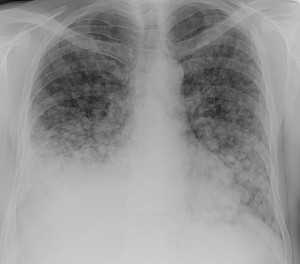

Как выглядят метастазы в легких на рентгене? Слева — узловые образования у пациента с раком яичка. Справа - метастазы рака яичников гематогенного характера с выраженным опухолевым лимфангиитом (обратите внимание на деформированный сетчатый, линейный характер легочного рисунка).